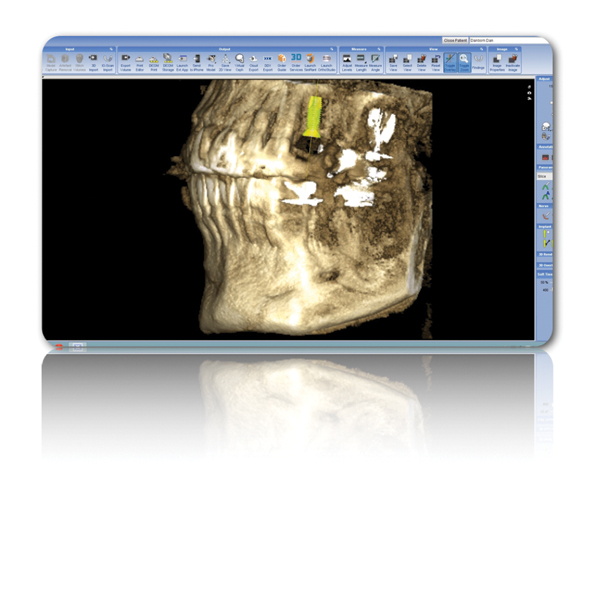

Figure 3 Examples of using digital workflow to import restoration data and plan implant treatment: the intraoral scan (IOS) data pinned to the CBCT (Fig 3); the designed ideal restoration being imported into the CBCT (Fig 4); the implant placed with the restoration and IOS toggled off (Fig 5).

Figure 3

Figure 4 Examples of using digital workflow to import restoration data and plan implant treatment: the intraoral scan (IOS) data pinned to the CBCT (Fig 3); the designed ideal restoration being imported into the CBCT (Fig 4); the implant placed with the restoration and IOS toggled off (Fig 5).

Figure 4

Figure 5 Examples of using digital workflow to import restoration data and plan implant treatment: the intraoral scan (IOS) data pinned to the CBCT (Fig 3); the designed ideal restoration being imported into the CBCT (Fig 4); the implant placed with the restoration and IOS toggled off (Fig 5).

Figure 5

Although workflows can vary, in many implant cases, typically a CBCT scan of the area of concern is made. Then, with an intraoral scan or digital version of a model or impression, the practitioner begins working with the design software of the particular intraoral scan or CBCT system being used (Figure 3 through Figure 5). The edentulous area or area where teeth are to be extracted can then be thoroughly evaluated. Ideal restorations can then be previsualized or treatment planned from both an esthetic and functional standpoint. Once this is done, the intraoral information is pinned or overlaid onto the CBCT scan. The restoration(s) can then be imported into the software system, toggled on or off—ie, shown or not—and the underlying bone evaluated.3